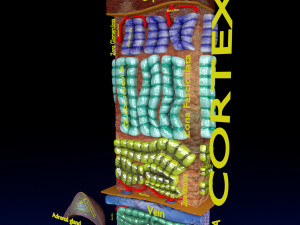

This is a 1:1 scaled model of right breast cut opened in sagittal plane to reveal its internal antomy and histology (schematic). The deeper parts and fascial layers are also depicted to give a very detailed approach to the model. The full layers starting from skin, nipple areola, till intercodtal muscles and ribs are also depicted.